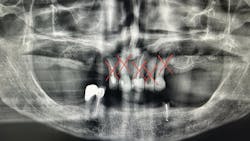

For many older adults, the transition to complete edentulism (figure 1) is both a clinical and emotional hurdle. It often brings feelings of grief, loss of identity, and a gradual detachment from routine dental care. However, this stage should not signal the end of the dental hygienist’s involvement. On the contrary, it requires heightened attention.